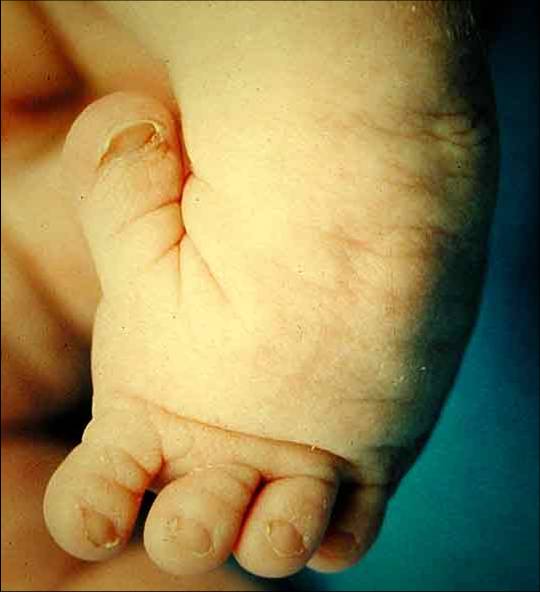

• skewfoot (serpentine or Z foot)

• tarsometatarsal adductus and valgus hindfoot

• rigid clubfeet (equinocavovarus)